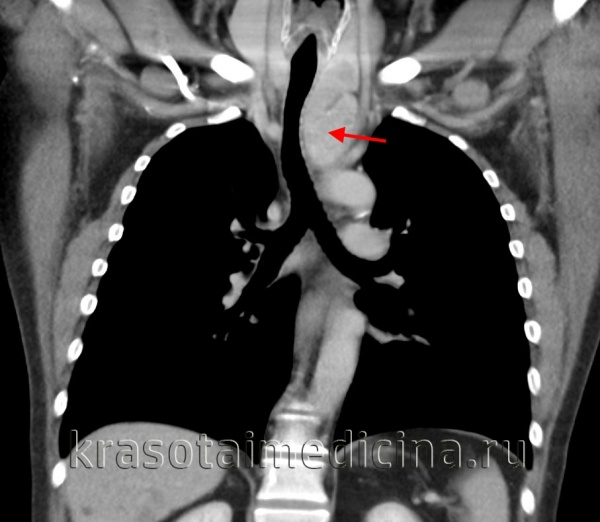

На компьютерных томограммах в аксиальной проекции визулизируются (Рис.7 — 13, 16-19):

1 – Правое легкое

2 – Левое легкое

4 — Левый главный бронх

5 – Правый главный бронх

6 – Непарная вена

7 — Нисходящая часть аорты

8 – Восходящая часть аорты

9 – Левый желудочек сердца

10 – Левое предсердие

11 – Правый желудочек

12 – Правое предсердие

13 – Легочный ствол, с отходящими от него левой и правой легочными артериями

15 – Плечеголовной ствол

16 – Левая общая сонная артерия

17 – Левая подключичная артерия

18 – Правая общая сонная артерия

19 – Правая подключичная артерия

20 – Верхняя полая вена

21 – Левая плечеголовная вена

22 — Правая плечеголовная вена